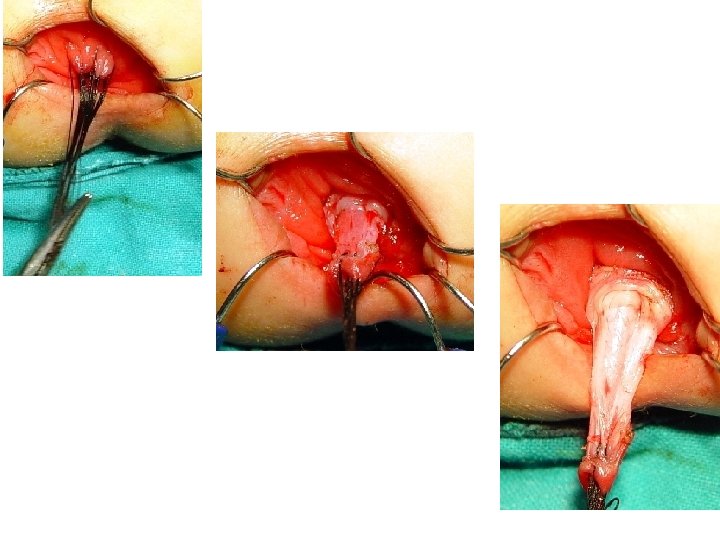

Treatment • Recently, one-stage pull-through with laparoscopic techniques. • More recently, a transanal endorectal pullthrough operation performed without opening the abdomen has been used with excellent results in rectosigmoid type

Operations • Swenson Procedure Resection of the aganglionic segment deep into the pelvis and direct end to- end anastomosis of the proximal colon to the anorectal canal. • Duhamel Procedure Aganglionic rectum is retained and the ganglionated bowel brought posteriorly and anastomosed to the aganglionic remnant in a side-to side

Operations Soave Procedure • The Soave with its variations, is the most frequently performed procedure in the world • It involves an extramucosal resection of a retained • aganglionic rectal segment. • The rectal mucosa is removed and a muscular cuff retained. • The ganglionated colon is brought through this cuff and anastomosed to the dentate line in the rectum, • Its variant is laparscopic assisted and endorectal pull through